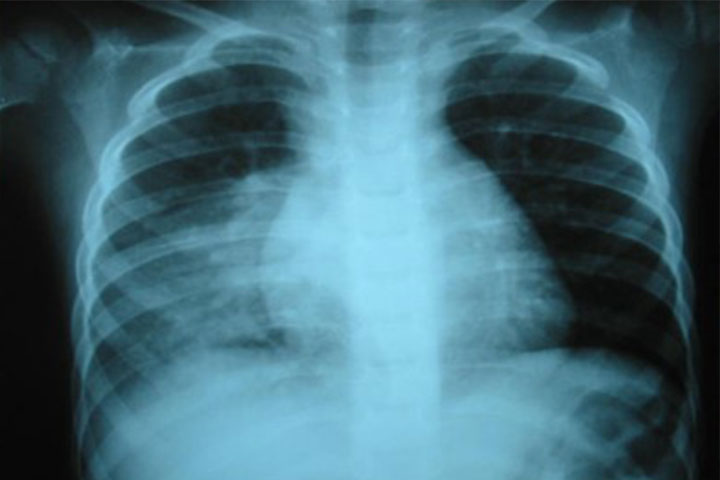

12 de noviembre, Día Mundial contra la Neumonía

En el Día Mundial contra la Neumonía, la Secretaría de Salud de Michoacán (SSM) invita a la población a cuidarse y extremar precauciones en esta temporada de frío, con la vacunación temprana, con una alimentación adecuada y mediante el control de factores ambientales, como los cambios de temperatura y al evitar las corrientes de aire. Según explicó Cirilo Pineda Tapia, coordinador del Programa de Atención a la Salud de la Infancia y...